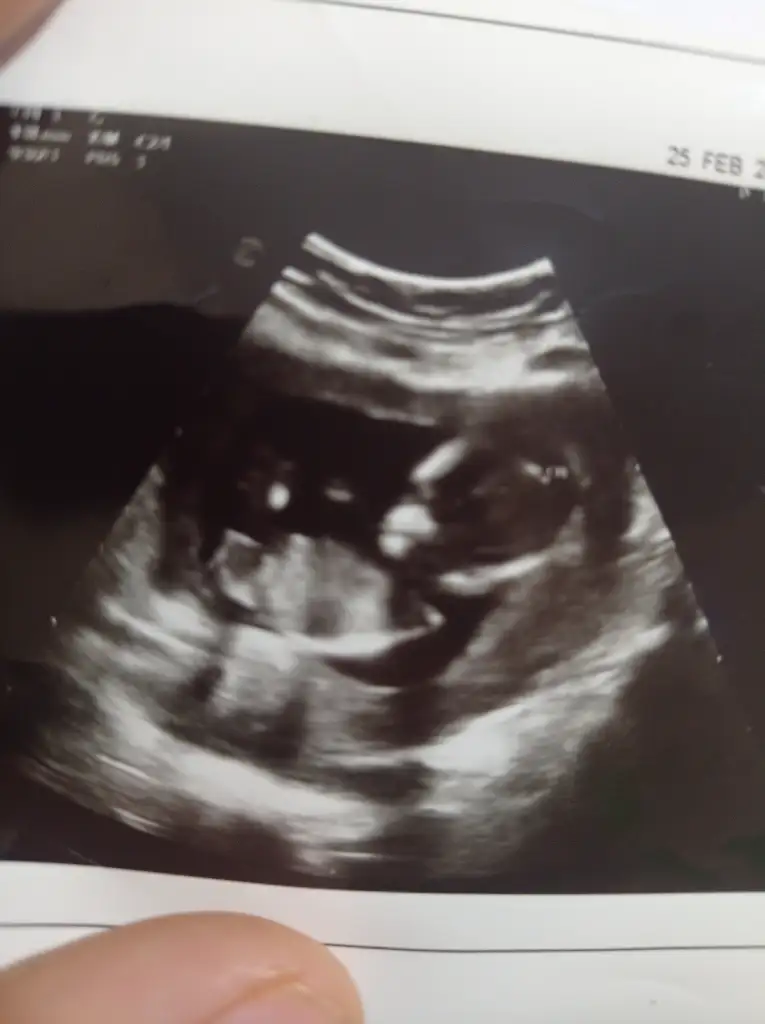

Belli oldu mu cinsiyetiniz acaba?İyi günler ben 24 haftalık biturlu gözükmüyor cinsiyeti bakabilirmisiniz

Bende bilmiyorum daha bir erkek bir kız diyorlar görünüşe göre doğumda ögrenecemCinsiyetiniz belli oldu muu, ben erkek gördüm sanki burada

Malesef bilmiyorum doktorlar net birşey demedi sağlıklı olsunda herşeyin hayırlısı artık doğumda ögrenecem bu gidişleAma 29. Haftadasınız sanırım erkekse zaten çok net belli olmazmı yani pipi yoksa kızdır